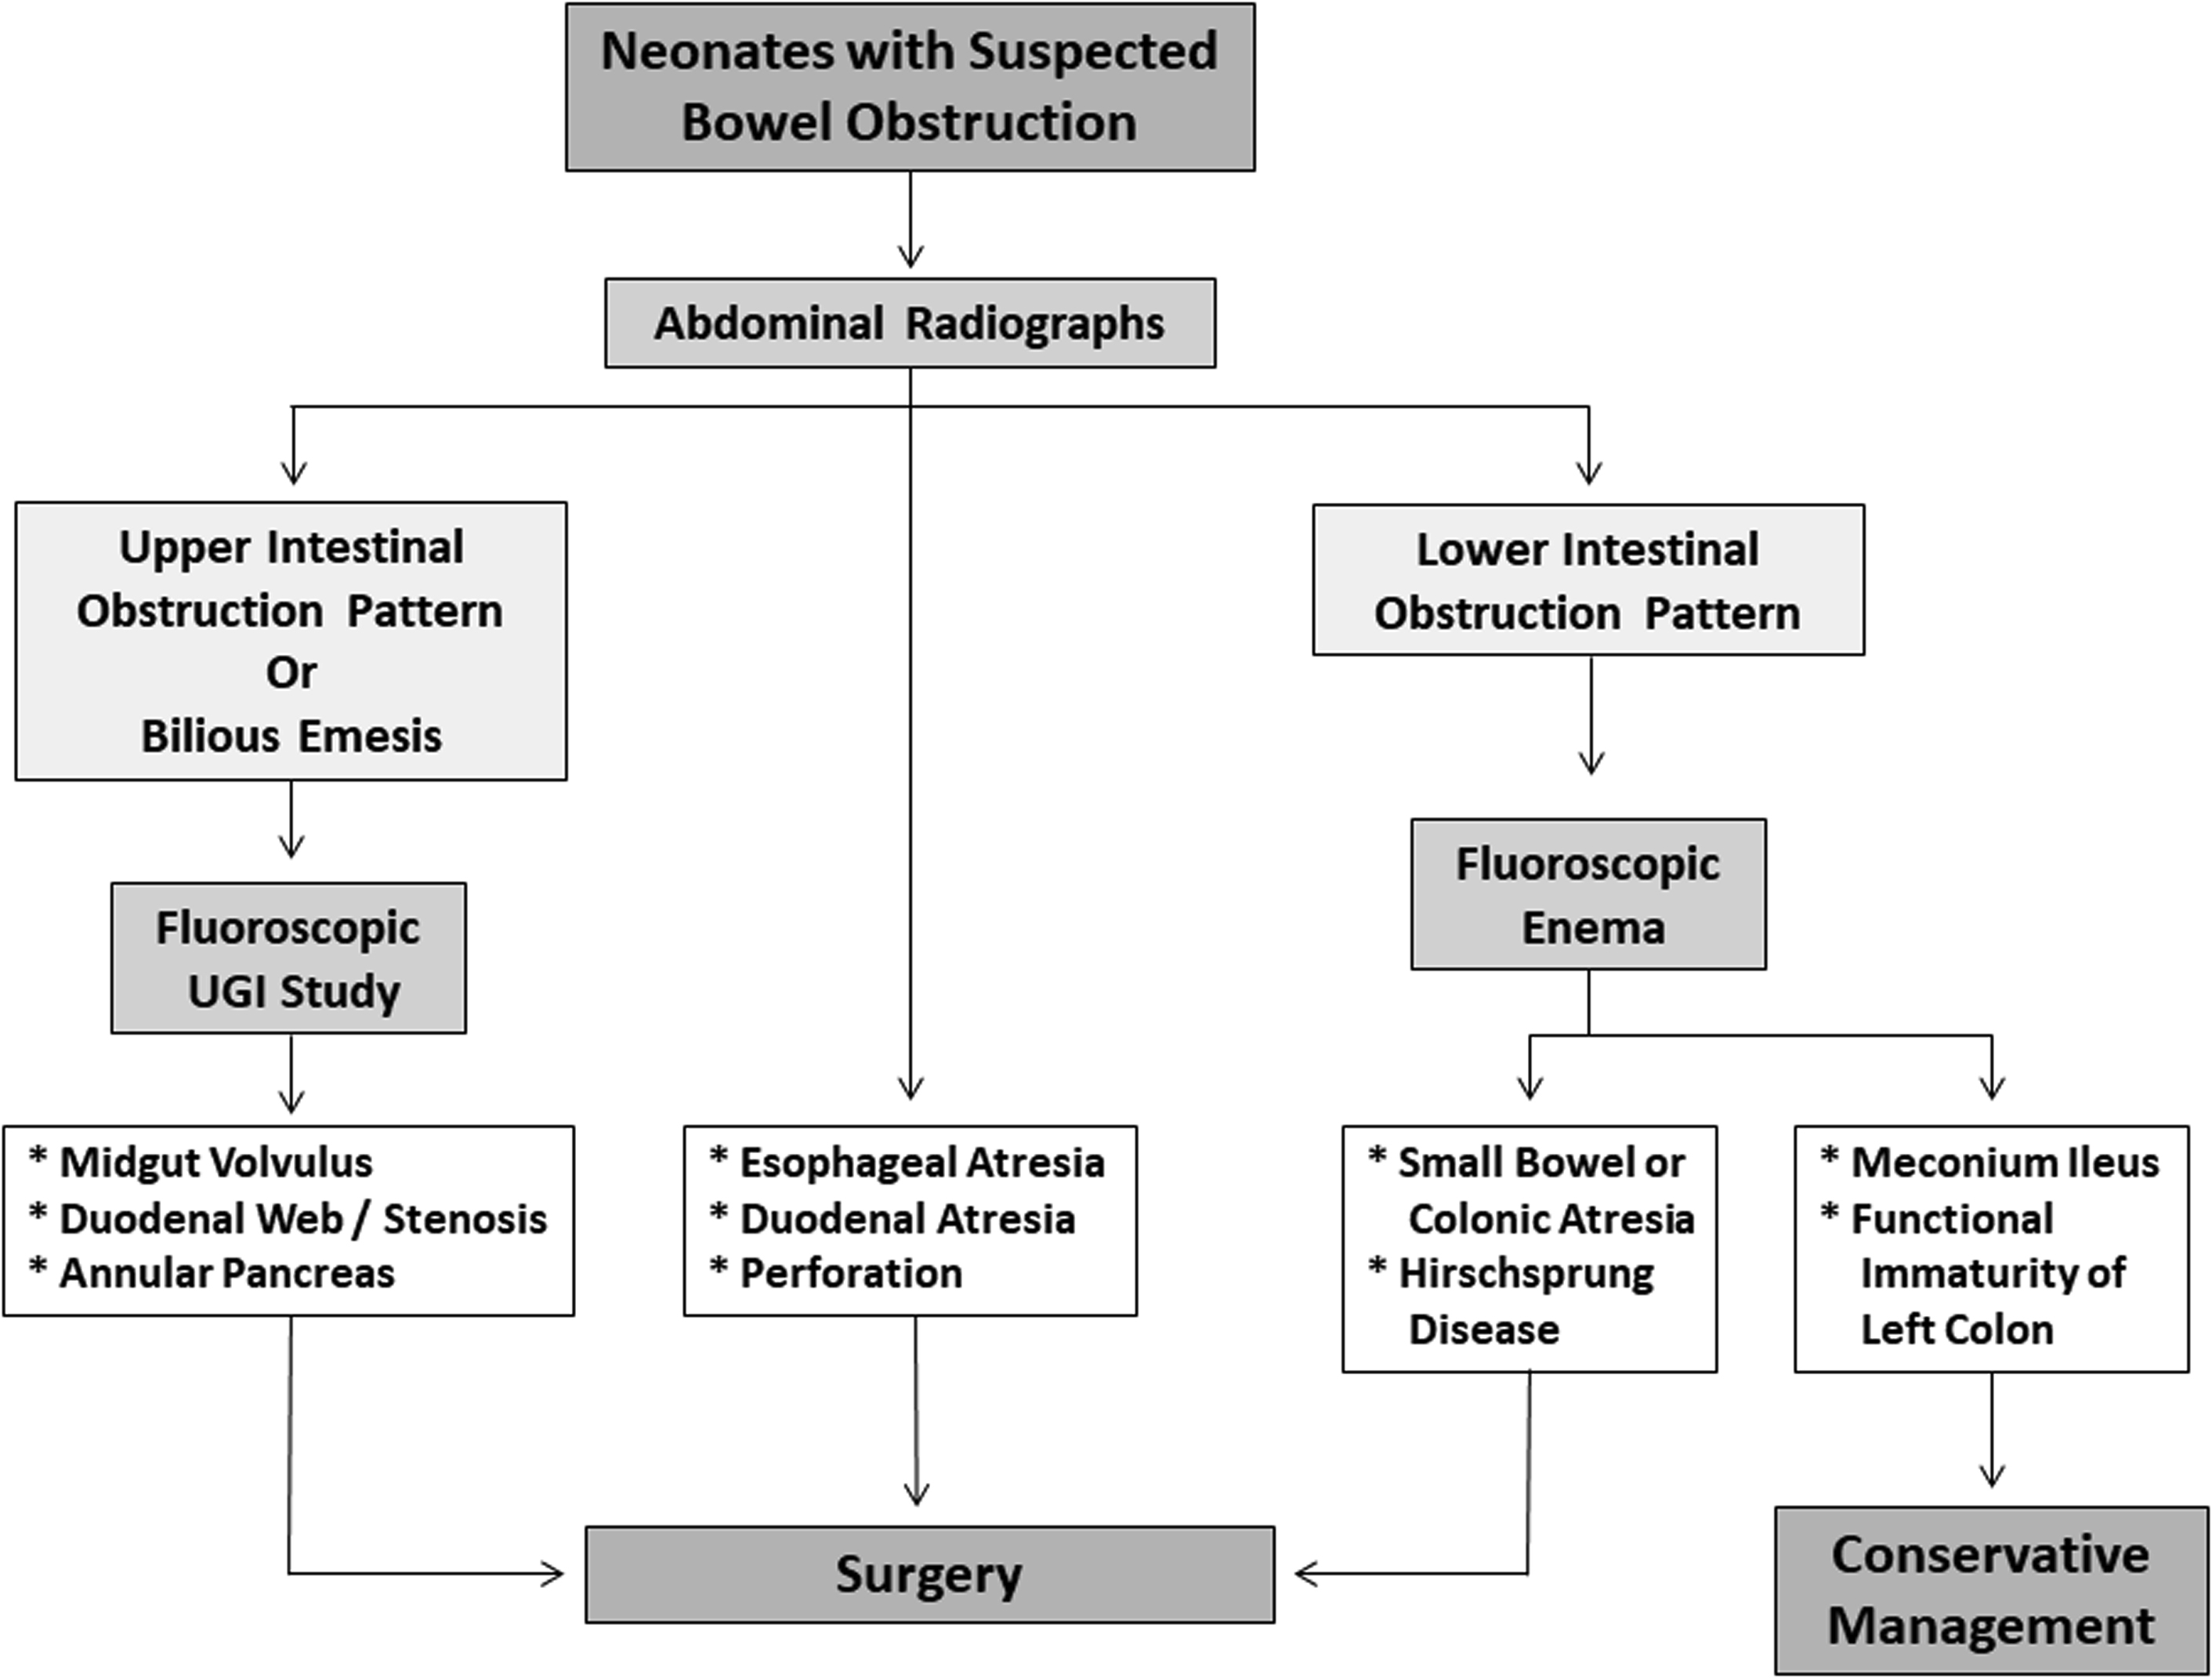

Bowel Obstruction Intestinal Obstruction MedlinePlus

Small Bowel Obstruction